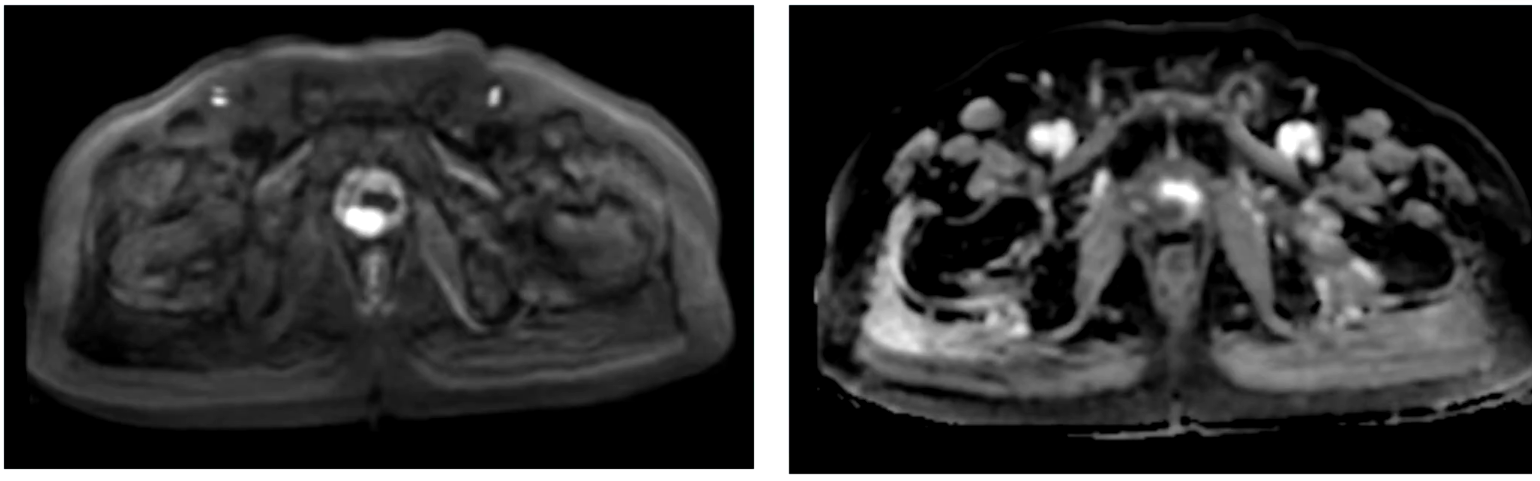

骨扫描

1. T9放射性增高,良性病变可能大,请结合临床、定期复查;

2. L5-S1椎体近关节面骨质增生伴放射性增高,考虑退行性病变所致;

3. 腰椎退行性改变;骨质疏松待排建议骨密度测定。